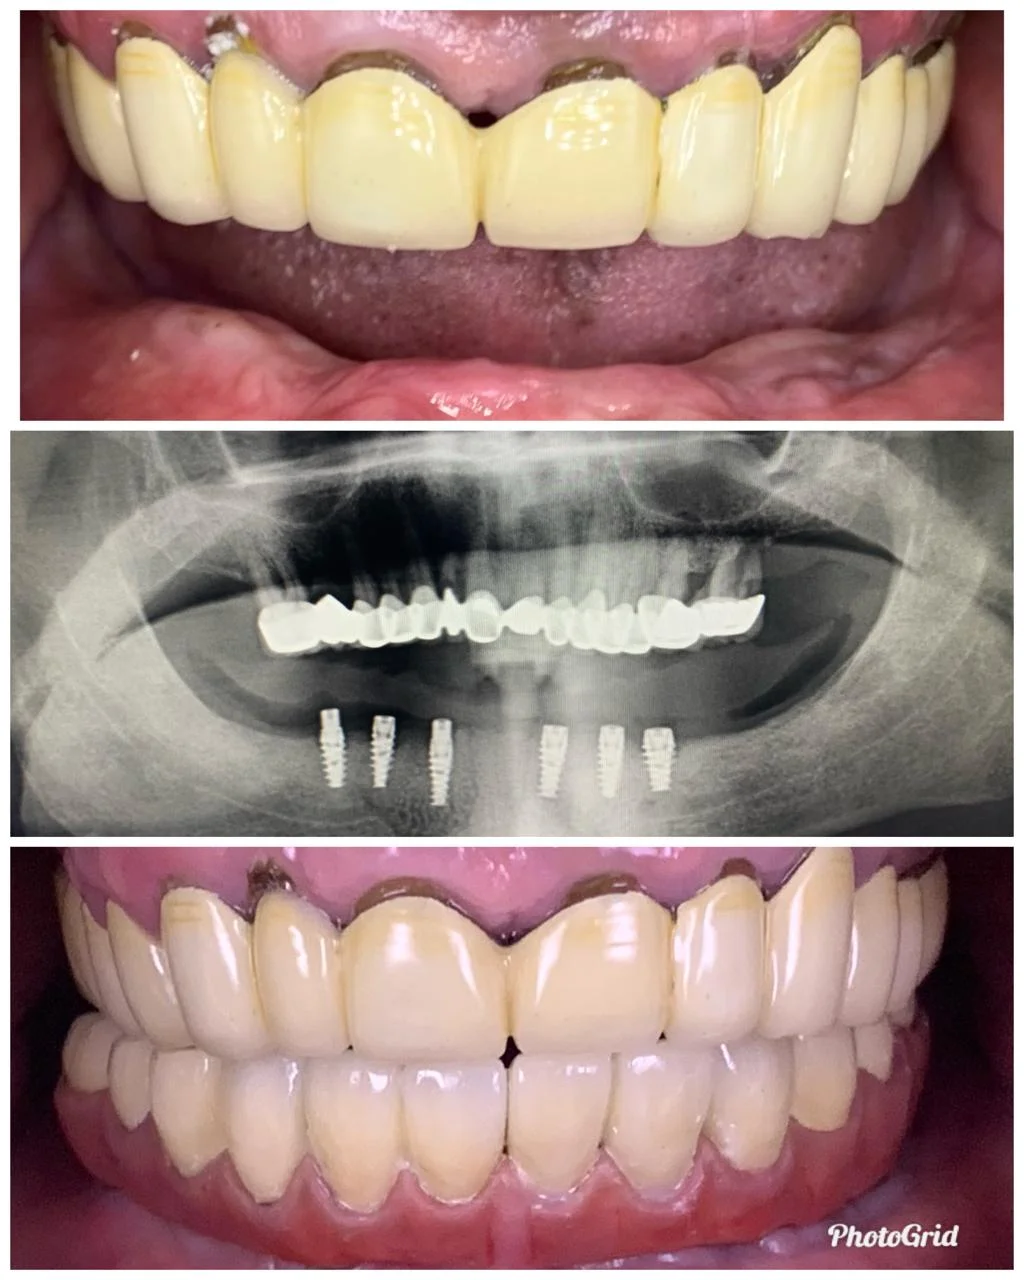

Showing Our Expertise In Dental Implantology

All-on-4 Implants (Per Jaw)

All-on-6 Implants (Per Jaw)